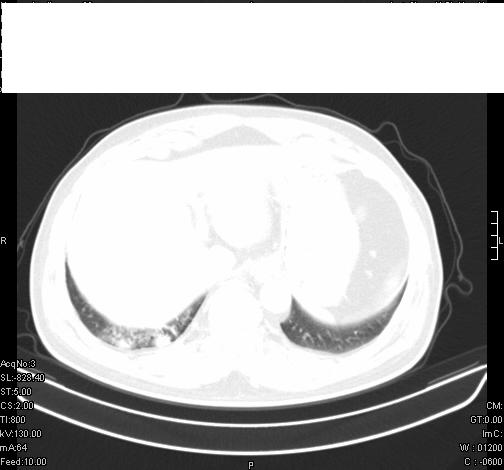

标题: CT6685:右肺阻塞性炎症,增强CT。 [打印本页]

标题: CT6685:右肺阻塞性炎症,增强CT。

前几天,发了患者的平扫片,患者抗炎一周后增强扫描。右中叶病灶吸收明显,但下叶病灶未见明显吸收。右肺门可见结节影,看来凶多吉少

右肺下叶散在的斑片状致密影,下叶支气管变窄。考虑:右肺慢性炎症。

右肺下叶支气管壁不规则增厚,右肺下叶有斑片状影分布。考虑右肺中央型肺癌伴右肺下叶阻塞性改变。建议支纤镜检查。平扫比增强较好显示了病变情况。

既然抗炎治疗有效,可继续治疗;右肺下叶支气管管腔狭窄,管壁增厚,右下肺见斑片状高密度影,右侧主支气管后见结节影(淋巴结?),肺癌不能排出。